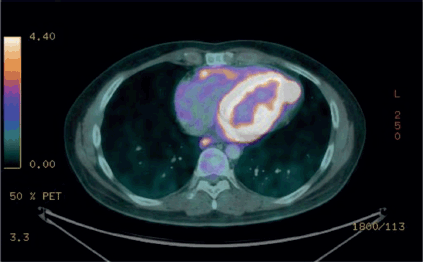

Figure 3. FDG PET scan with increase in both the size and metabolic tumor volume of the pericardial lesions which have heterogeneous density, predominantly hypodense, with persistent abnormal radiotracer uptake and a SULmax of 14.5 and VTM of 77.3.

Following the complete response, the patient was placed under surveillance. However, the patient was lost to follow-up, and after 9 months, presented with disease recurrence, evidenced by an increase in the pericardial mass size, elevated metabolic activity and worsened lymph node involvement. Second-line therapy with pazopanib combined with trabectedin was initiated, but after 4 cycles, the patient experienced local progression in the pericardium and metastasis to the brain.

The most recent PET-CT examination (Figure 3) showed a significant increase in both the size and metabolic tumour volume of the pericardial lesions, indicating disease progression. Given these findings and the worsening clinical course, the treatment plan included whole-brain radiotherapy and the initiation of systemic therapy with Pazopanib.